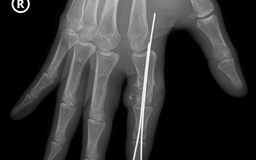

Cứu sống ngón tay thủy thủ bị đứt rời sau 25 giờ